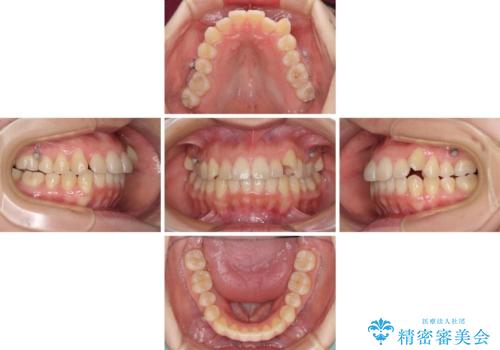

- 八重歯と前歯のデコボコを気にして来院された患者様です。

八重歯の他に、上顎歯列を狭窄しているという問題点がありました。

また、八重歯により上顎奥歯が前方に位置しており、咬み合わせの改善も必要な状況でした。